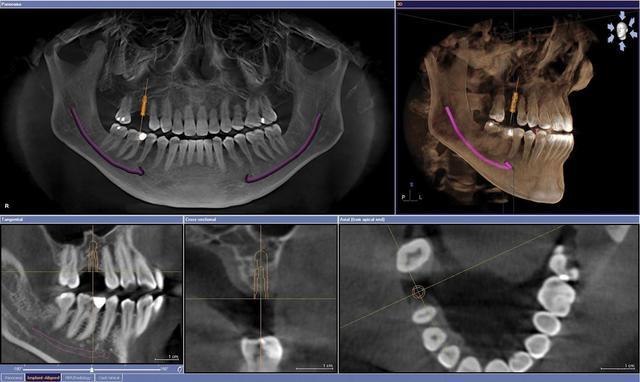

• TAC DENTAL

TAC DENTAL

El comienzo de las aplicaciones como la cirugía e implantología guiadas y asistidas por ordenador, introducidas a raíz de los trabajos elaborados en el Proyecto Phidias, comenzado en 1998su difusión mundial, inundándose todo el sector dental con otros productos de los demás fabricantes (i-CAT-ISI, CB-Mercuary-Hitachi, 3D-Accuitomo-JMorita, Picasso-Vatech-Ewoo, Iluma-Kodak, Galileos-Sirona, Planmeca,etc.).